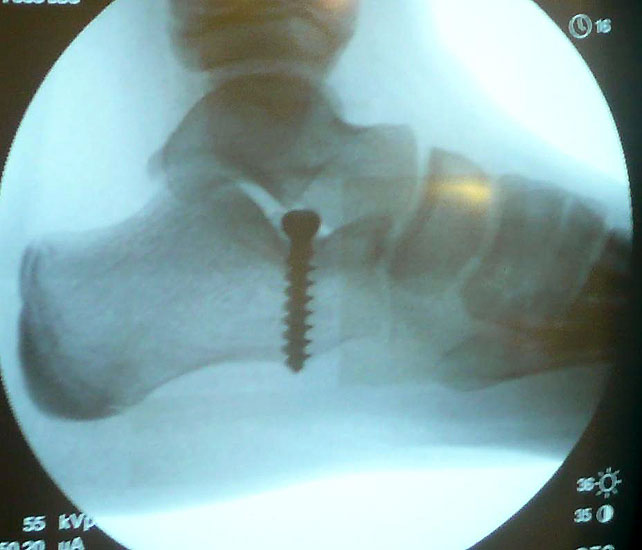

Abwaschen und steriles Abdecken beider Füße in Rückenlage und Unterschenkelblutleere (Abb. 1). Ertasten des Sinus Tarsi, zur genaueren Lokalisation Verwendung einer Kanüle (Abb. 2) um die korrekte Position über dem Eingang zum Sinus tarsi unter Bildverstärker zu kontrollieren. Über einen 1-2cm messenden Hautschnitt (Abb. 3) erfolgt nun die Präparation des Eingangs zum Sinus tarsi durch stumpfe Präparation. Die Knochenoberfläche des Calcaneus am tiefsten Punkt des Sinus tarsi wird dargestellt, unterstützt durch eine manuelle Rückfußinversion. Nach Markieren der korrekten Eintrittstelle mit einem Kirschnerdraht und anschließender Bildwandlerkontrolle (Abb. 4) wird nun die calcaneare Eintrittstelle in ca 20° Kippung nach lateral und dorsal mit einem 3,2mm Bohrer aufgebohrt.

Hierbei ist darauf zu achten, einerseits den Eintrittspunkt nicht zu weit lateral zu wählen um eine Aussprengung der lateralen Calcaneus-Corticalis oder Kompromittierung der Peronealsehnen beim Bohren oder Eindrehen der Spongiosaschraube zu vermeiden, andererseits das Calcaneo-cuboidale Gelenk (C-C-Gelenk) nicht zu verletzen. Nach Gewindeschneiden und Längenmessen Einbringen einer 6,5 mm Titan-Spongiosaschraube mit durchgehendem Gewinde und einer Länge von durchschnittlich 25 bis 35mm. Der Abstand zum C-C Gelenk sollte mindestens 10 mm betragen.

Die Schraube muss so weit eingedreht werden, dass sich der Schraubenkopf nach Aufheben der manuellen Rückfussinversion genau unter dem Processus lateralis tali befindet und eine pathologische Eversion des Rückfußes durch Anschlag des Schraubenkopfes am processus lateralis tali verhindert wird (Abb. 5). Eine zusätzliche Kontrolle der korrekten Schraubenposition kann klinisch am ausgestreckten Bein (mit Streckung des Kniegelenkes)erfolgen:

Bei persistierender Valgusstellung des Calcaneus muß die Schraube aus dem Knochen dosiert ausgedreht werden, bei Varusstellung des Calcaneus muß die Schraube weiter eingedreht werden. Nach dem Hautverschluß wird das Bein elastokompressiv gewickelt (Abb. 6).